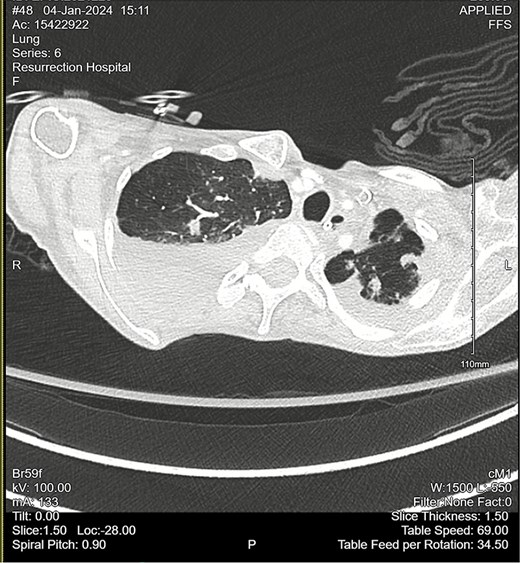

Computed tomography (CT) angiogram of the chest demonstrated numerous small nodular and patchy opacities throughout the upper lobes ranging from punctate to 1.2 cm in diameter (Figs 1 and 2). Additionally, bilateral pleural effusions with extensive atelectasis were also observed.

CT chest angiogram with axial cross-section demonstrating bilateral pulmonary nodules and scattered ground-glass lesions in the upper lobes. No signs of embolism in the pulmonary arterial segments. Reduced lung volumes secondary to bilateral pleural effusions are observed.